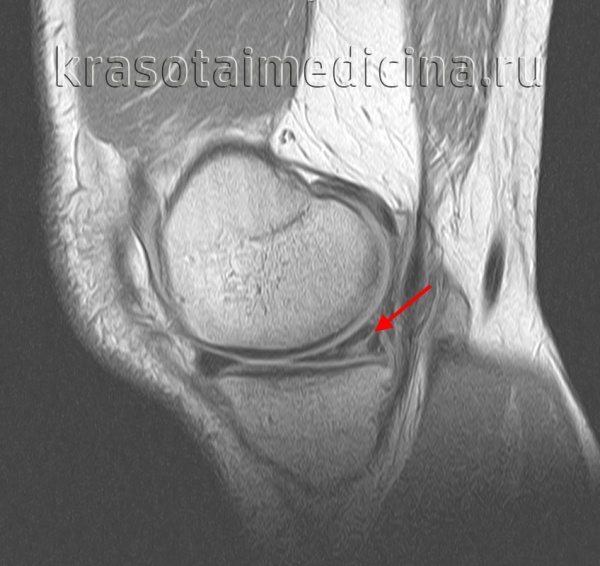

(Слева) МРТ PDВИ, сагиттальный срез: у пациента с разрывом передней крестообразной связки (ПКС) (изображение отсутствует) определяется периферический ВПР медиального мениска. Центральный фрагмент мениска достаточно крупный настолько, что мог быть ошибочно принят за целый задний рог и интерпретирован как неповрежденный.

(Справа) МРТ Т2ВИ, режим подавления сигнала от жира, сагиттальный срез: у этого же пациента определяется гиперинтенсивный сигнал от разрыва и темная ткань мениска на периферии разрыва. Периферический ВПР может быть с легкостью определяться на последовательностях чувствительных к жидкости. (Слева) MPT PDBИ, сагиттальный срез: определяется вертикальный продольный разрыв заднего отдела медиального мениска. Этот разрыв немного смещен. Небольшой периферический фрагмент мениска позволяет отличить данный разрыв от отделения мениска от капсулы.